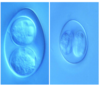

Coccidiosis of ruminants

Oocysts in a camel

Thicker walls seen for survival in desert like conditions

Coccidiosis of ruminants

Oocysts in a camel

Thicker walls seen for survival in desert like conditions

Eimeria

Eimeria Cameli

Thick wall with well seen cap

Eimeria Cameli

Thick wall and well seen cap